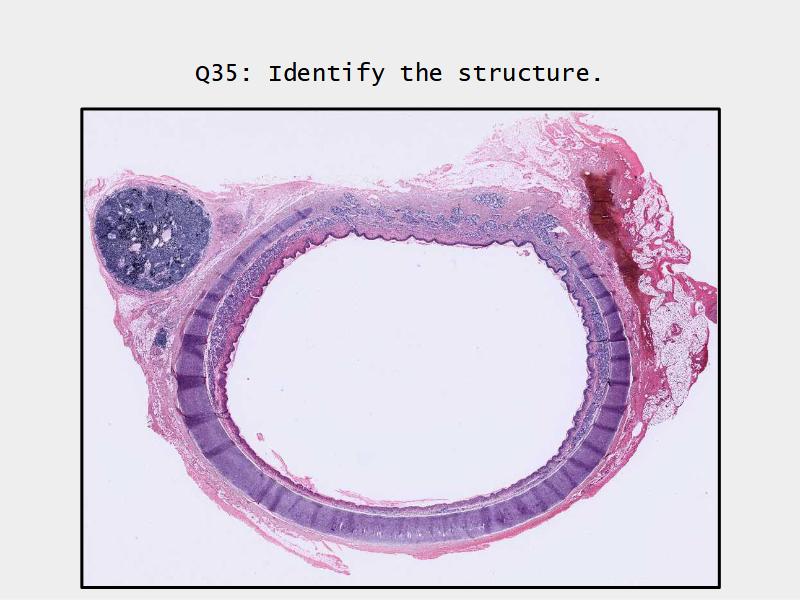

Trachea

Respiratory epithelium

- Pseudostratified

- Ciliated

- Columnar

- Epithelium with

- 4 Cells

- Ciliated columnar cells

- Non-ciliated columnar cells

- Goblet cells

- Basal cells